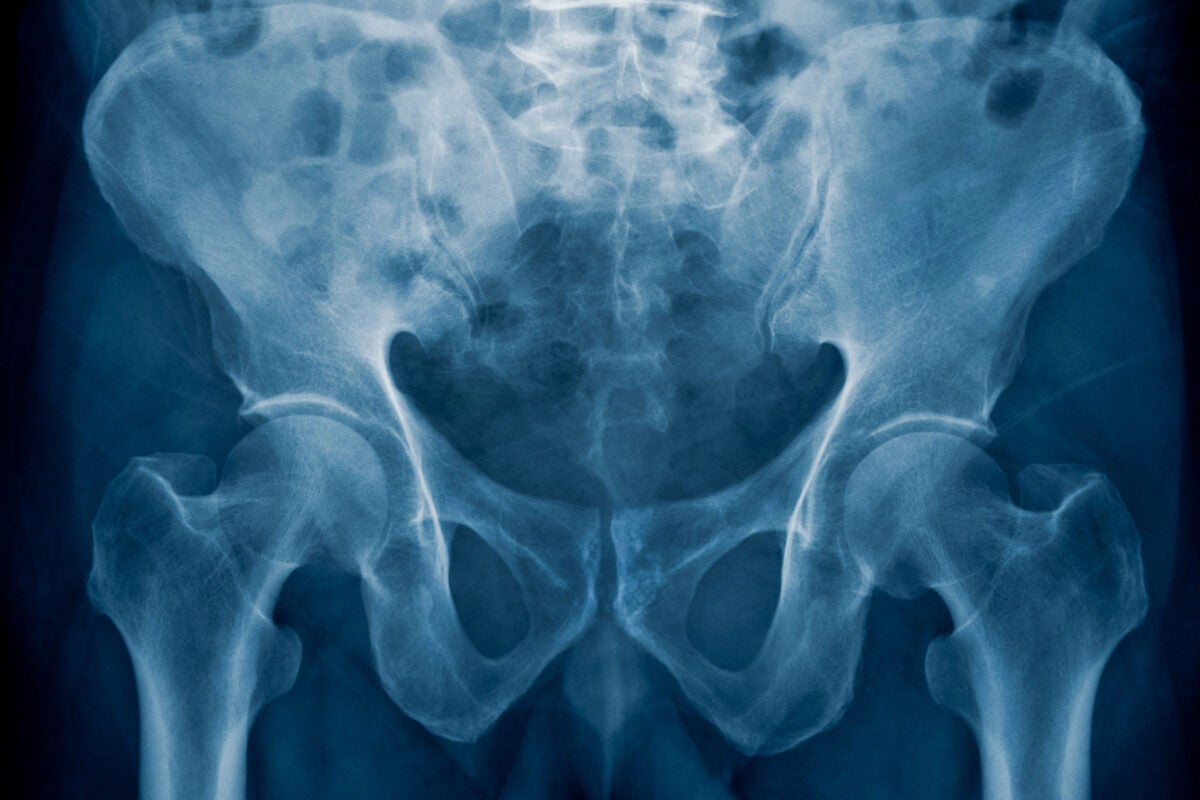

骨盆的弯曲和盆状形状是人类独有的。

研究表明,这些特征中有许多是在怀孕6到8周左右形成的。这包括人类独有的关键骨盆特征,如弯曲和盆状的形状。在这一点上,骨骼仍然是软骨,所以它们可以很容易地弯曲、旋转、扩展和生长。

研究人员进行了RNA测序,以显示该区域的哪些基因触发了骨盆的形成和延缓骨化。他们发现,在6到8周的时间里,有数百个基因会被打开或关闭,从而形成骨盆中的髂骨。髂骨是髋关节最大最上面的骨头,具有叶片状结构,弯曲并旋转成盆状,以支持用两条腿走路。

与黑猩猩和大猩猩相比,我们的骨盆刀片更短更宽的方向使人类可以直立行走和保持平衡,而不必将重心向前转移,并使用指关节来保持稳定和平衡。它还有助于增加产道的大小。